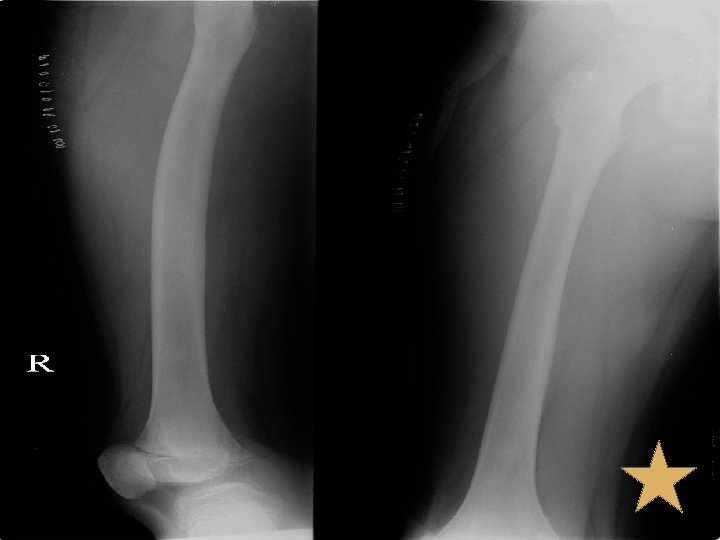

Bone Scan v. Bone scan (17/08/52) v. Bone lesion at skull is corresponding with multiple geographic lytic lesions without sclerotic rim and some blastic lesions in diploic space of bilateral parietal bone, likely bone metastases. Bone lesion at C 2 vertebral body, pelvic rim, right acetabulum, head, proximal, mid shaft and distal right femur, likely due to bone metastases as correlated with lytic lesion seen on PET/CT.

Progression v 03/08/52 Start Radiotherapy at tonsils and lymph node 70 Gy v 06/08/52 รบ consult at OPD ผปวยมปญหาเรองปวดทขาขางขวาต งแตตนขาถงปลายขา ไมมปวดบรเวณอน § CBC: Hb 8. 8 g/dl , WBC 11, 800 cells/mm 3 (N 78. 3 %, L 14. 9 %, M 3. 6% , E 2. 9% , B 0. 3% ), Platelet 122, 000 cells/mm 3 § LD-PRC 300 ml IV drip in 3 hour

Progression v 7/8/52 CBC: Hb 11 g/dl , WBC 9, 850 /mm 3 (N 66 %, L 21 %, M 3% , E 7% , AL 3% ), Platelet 104, 000 /mm 3 PTT 36. 8 sec [30. 4] PT 15. 4 sec [13. 4] Fibrinogen 641 mg/dl D-dimer 0. 2 mcg/dl [< 0. 3] v 10/08/52 OPD Follow up ผปวยยงมอาการปวดขาไมดขน Bonefos (800) 2 cap oral OD เชา

Progression v 20/08/52 OPD Follow up, ปวดขามากโดยเฉพาะทบรเวณนอง admit for further investigation § § § , ซดลง Investigation : plain X-ray leg [right], นด U/S right leg Consult pain: MO IV prn for pain Blood component as needed Continue Bonefos Continue Radiation